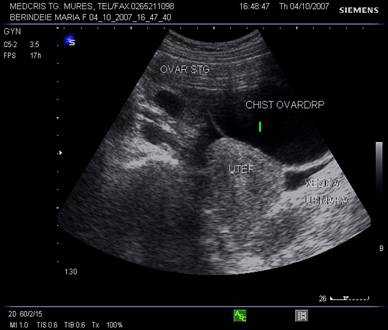

Tumorile ovariene

Ecografia abdominala si transvaginala trebuie sa raspunda suspiciunilor legate de malignitate sau benignitate. In functie de tipul de ecogenitate interna, tumorile ovariene se pot clasifica in [2,5,6] :

tumori ovariene pur chistice

tumori ovariene pur solide

tumori mixte ovariene

Fig. nr.387. Formatiune anecogena uniloculara cu perete subtire ( sageata ), fara lichid in Douglas ( chist functional , la o pacienta de 15 ani , la ecografia abdominala

Fig. nr.388. Chist ovarian anecogen , unilocular , cu perete subtire la ecografia transvaginala